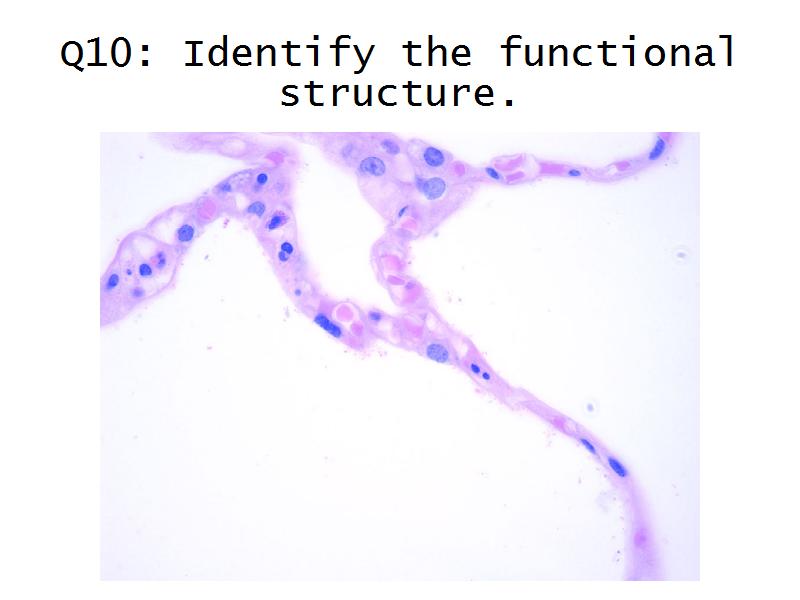

Kidney

Kidney

Slides 28 & 76

Kidney: Objectives

- Basic arrangement of nephrons and collecting tubules in the kidney

- Structure of the nephron and collecting tubules

- The renal corpuscle